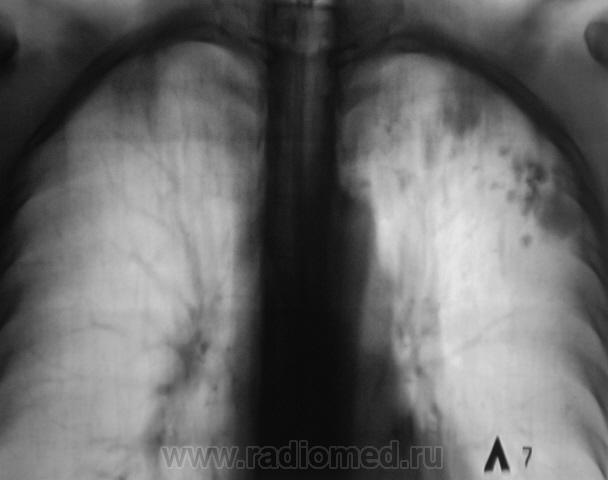

Пациент прооперирован - лобъектомия.